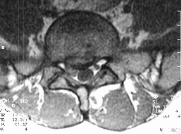

this point. She denied LE weakness or bowel/bladder dysfunction. MRI (L5-S1)

shows a right disc herniation with nerve root impingement Myleogram reveals

nerve root impingement.